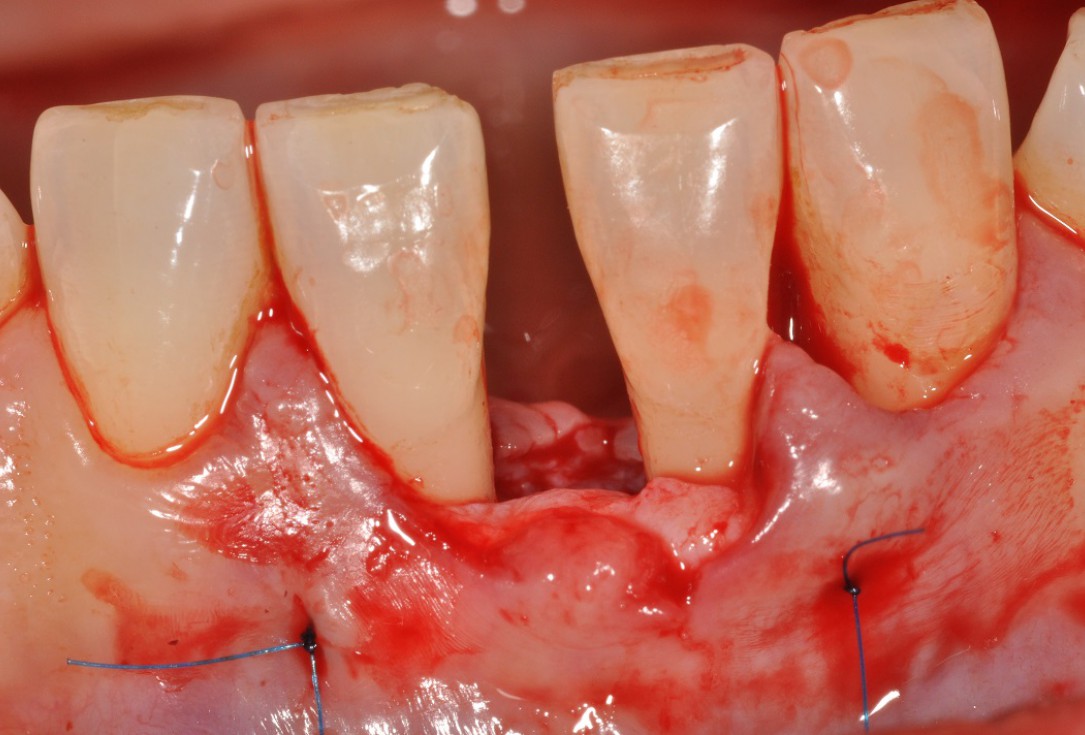

03/13 - Flap elevation and presentation of the defect.

Wide intrabony defect treated with the modified papilla preservation flap in conjunction with Straumann® Emdogain® and autogenous bone - Dr. B. Molnar